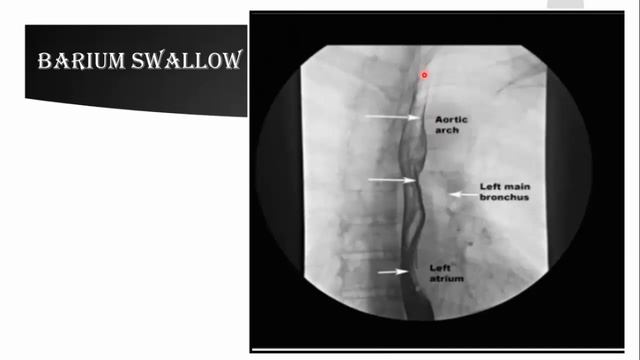

Radiological anatomy (plain X-ray & barium) of GIT смотреть онлайн

07:52

Radiological anatomy (plain X-ray & barium) of GIT

Freelance мастер-классы 18 просмотров